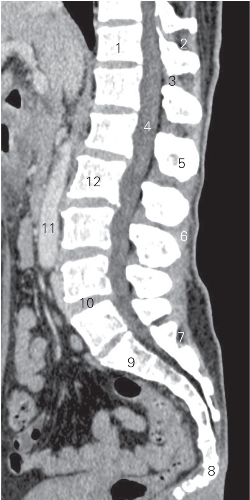

图3-5 经腰段脊柱正中矢状断层CT图像(软组织窗)

1 第11胸椎椎体 11th thoracic vertebral body

2 胸棘间肌 thoracic interspinal muscle 3 黄韧带 ligamentum flavum

4 硬膜囊 dural sac

5 第1腰椎棘突 1st lumbar spinous process

6 棘上韧带 supraspinous ligament 7 骶后孔 posterior sacral foramina

8 第1尾椎 1st caudal vertebrae

9 第1骶椎椎体 1st sacral vertebral body

10 第4腰椎间盘 4th lumbar intervertebral disc

11 腹主动脉 abdominal aorta

12 第2腰椎椎体 2nd lumbar vertebral body